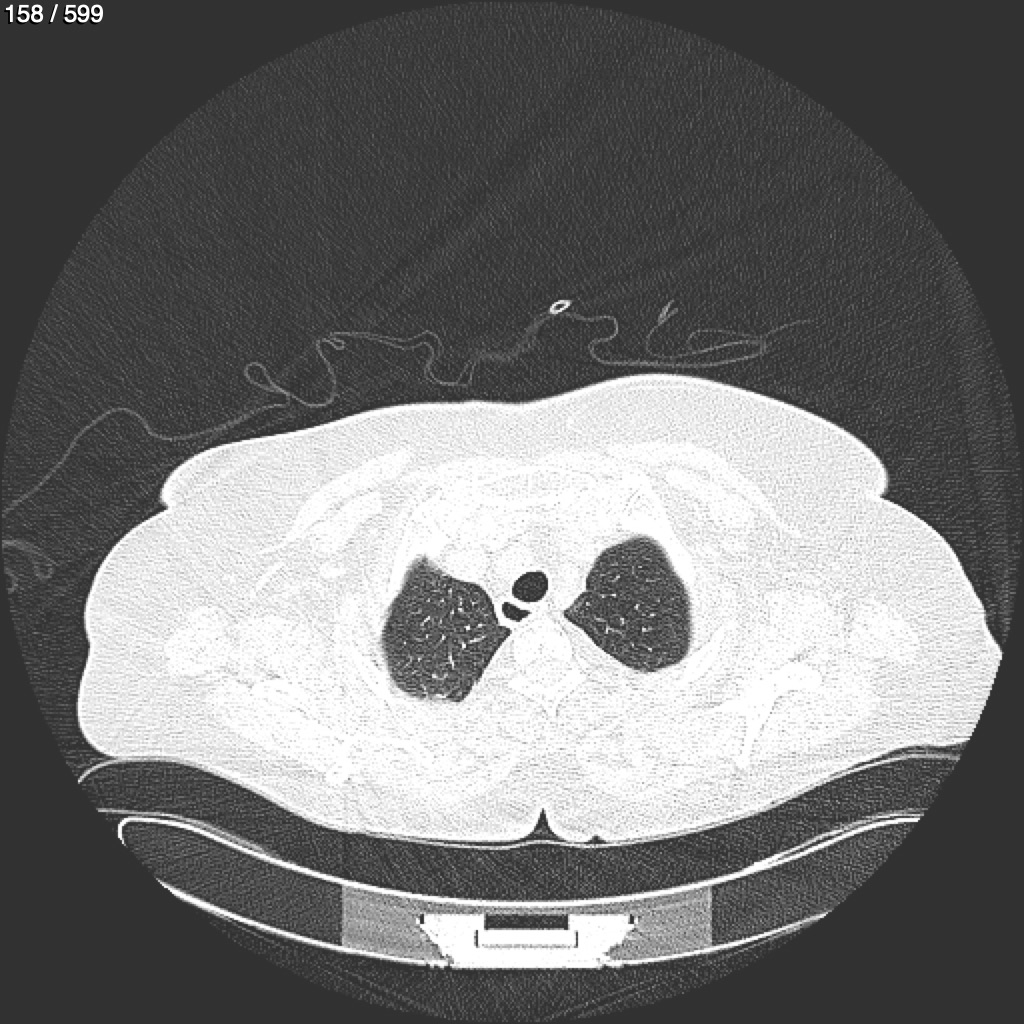

Home G​l​o​r​i​a​ ​G​l​a​d​y​s​ ​B​e​a​s​l​e​y​ ​-​ ​T​ó​r​a​x​ ​T​o​r​a​x​_​S​i​m​p​l​e​ ​(​A​d​u​l​t​o​)